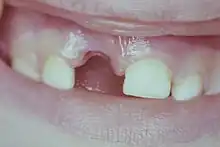

Fracture coronaire amélo-dentinaire avec exposition pulpaire

Fracture coronaire amélo-dentinaire avec exposition pulpaire : c'est une perte de substance coronaire avec douleurs aiguë et spontanée et plus ou moins de saignement pulpaire.